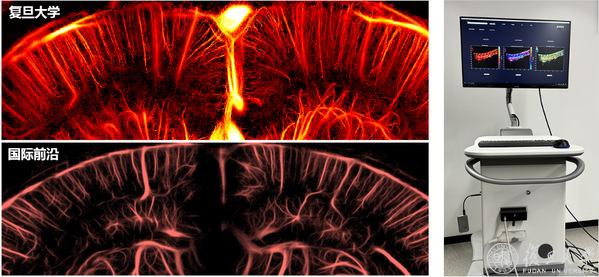

许凯亮团队研发超快超分辨经颅脑功能超声已实现成果转化

许凯亮研究员突破超声成像极限,打造的超高速、超分辨率超声成像脑机接口系统实现成果转化,助力科研与临床诊疗;加福民博士聚焦脑脊接口刺激器,完成植入式神经刺激器临床前试验;王守岩团队研发多项经颅、迷走、外周无创神经调控设备已经进入临床……